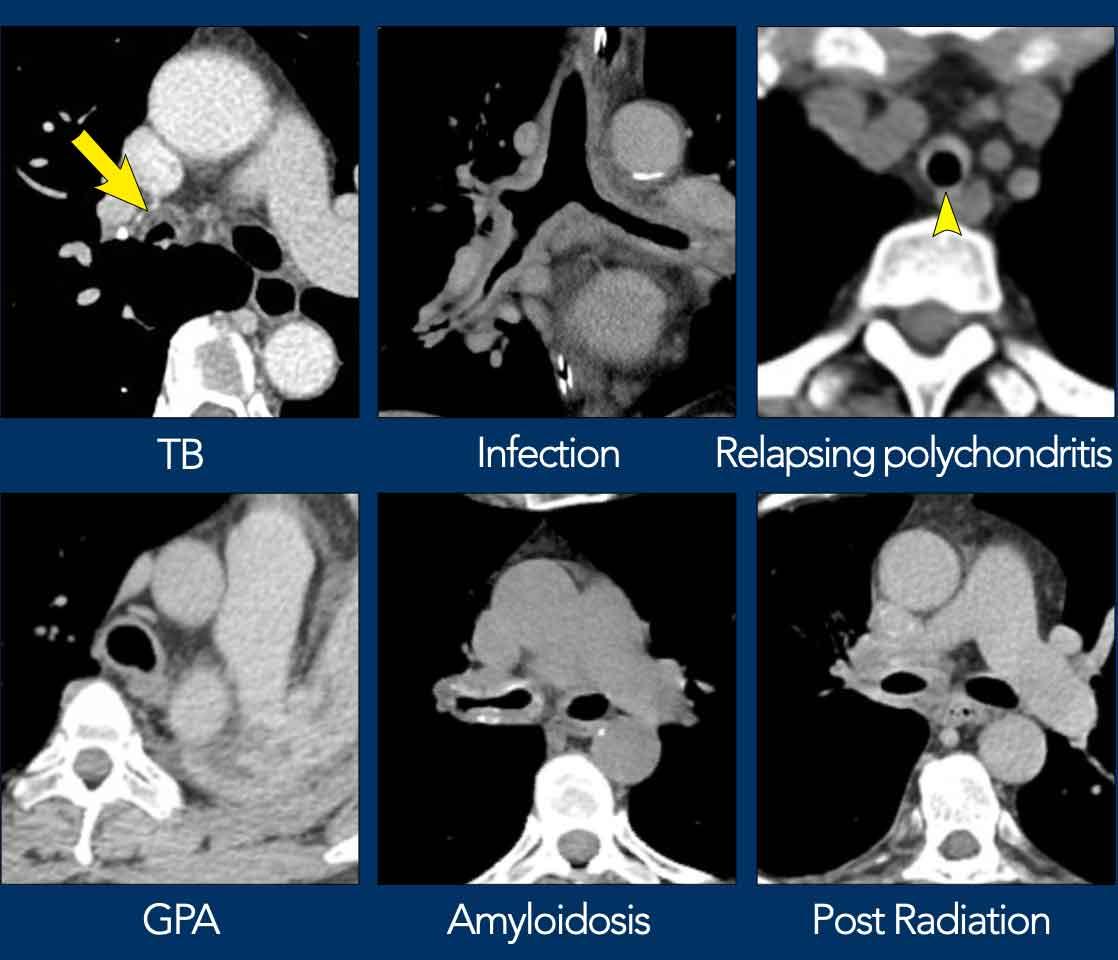

Dày thành – chẩn đoán phân biệt

Tại vị trí tổn thương, đường bờ bình thường vốn nhẵn và mỏng của thành khí quản và phế quản bị mất đi.

Chỉ một số ít bệnh có đặc điểm hình thái đặc trưng.

Dưới đây là một số ví dụ về dày thành đường thở trung tâm cả dạng khu trú lẫn lan tỏa.

- Viêm đa sụn tái phát có hình ảnh đặc trưng dạng móng ngựa.

- Bệnh amyloidosis biểu hiện dạng không đều rõ rệt kèm vôi hóa, gần như có tính chất đặc hiệu bệnh.

- Tổn thương do xạ trị giới hạn trong trường chiếu xạ.

Lao

Cũng như hầu hết các bệnh nhiễm trùng khác, các tác nhân gây nhiễm trùng khí phế quản có thể là vi khuẩn, nấm hoặc virus.

Viêm phế quản mắc phải tại cộng đồng chủ yếu do nhiễm virus. Đôi khi nhiễm trùng có thể liên quan đến các thủ thuật như mở khí quản, như minh họa ở hình bên trái.

Mặc dù lao có thể gây ra các bất thường ở đường thở trung tâm, viêm khí phế quản lao đơn độc là rất hiếm gặp.

Tổn thương đường thở trung tâm trong bệnh lao lồng ngực lan rộng hơn có khả năng xảy ra hơn, và có thể biểu hiện trên CT dưới dạng dày thành khu trú không đều hoặc dày thành lan tỏa hơn.

Trong giai đoạn mạn tính, tổn thương có thể dẫn đến hẹp đường thở khu trú do tái cấu trúc đường thở và hình thành xơ hóa phản ứng với loét các củ lao dưới niêm mạc.

Viêm

Viêm đa sụn tái phát

Viêm đa sụn tái phát là một rối loạn tự miễn ảnh hưởng đến sụn của đường thở trung tâm với các đợt viêm tái phát, có thể dẫn đến phá hủy và xơ hóa.

Do sụn ở các vị trí khác trong cơ thể cũng có thể bị ảnh hưởng, trên lâm sàng có thể gặp tổn thương tai và mũi (ví dụ: biến dạng mũi yên ngựa). Các bệnh lý tim mạch như bệnh van tim và phình động mạch chủ cũng có thể xảy ra.

Trên hình ảnh CT ngực, có thể thấy dày thành đường thở trung tâm với tỷ trọng mô mềm.

Các bất thường thường không ảnh hưởng đến thành sau vốn không có sụn.

Sau giai đoạn cấp tính, có thể hình thành vôi hóa và hẹp lòng đường thở, cũng như xẹp đường thở quá mức khi thở ra (tức là nhuyễn khí quản-phế quản) do phá hủy sụn.

U hạt kết hợp viêm đa mạch

U hạt kết hợp viêm đa mạch (GPA), trước đây được gọi là u hạt Wegener, là một bệnh viêm mạch hoại tử đa hệ thống ảnh hưởng đến các mạch máu cỡ vừa và nhỏ, với sự tổn thương xoang cạnh mũi, phổi và thận.

Trên lâm sàng, bệnh liên quan đến nồng độ c-ANCA tăng cao.

GPA có thể gây dày thành đường thở trung tâm theo chu vi không đều, có thể dẫn đến hẹp lòng đường thở ở giai đoạn muộn của bệnh.

Tổn thương này thường gặp ở khí quản dưới thanh môn nhưng cũng xảy ra ở phế quản gốc và phế quản thùy.

Các tổn thương phổi đồng thời bao gồm đông đặc có hang và kính mờ do viêm mạch – lần lượt do hoại tử và xuất huyết phế nang – là những dấu hiệu hữu ích để định hướng chẩn đoán phân biệt.

Bệnh amyloid

Bệnh amyloid khí quản-phế quản được đặc trưng bởi sự lắng đọng protein amyloid bất thường dưới niêm mạc.

Đây là một bệnh rất hiếm gặp, thường khu trú nhưng có thể liên quan đến bệnh amyloid hệ thống.

Sự lắng đọng protein có thể khu trú (dạng khối; u amyloid) hoặc lan tỏa và thâm nhiễm hơn.

Amyloid trong thành đường thở dẫn đến dày mô mềm đậm độ cao, vôi hóa và không đều rõ rệt trên hình ảnh CT.

Bệnh không có phương pháp điều trị triệt để, và các lựa chọn điều trị như xạ trị ngoài và nội soi phế quản cắt bỏ tổn thương tập trung vào việc hạn chế tắc nghẽn lòng đường thở nhằm giảm triệu chứng hô hấp.